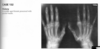

Anteroposterior view of the hands of a

patient with chronic renal failure shows subperi-

osteal resorption along the radial aspect of the

middle phalanges of the index and middle fingers

(Fig. 2.23.1, arrows). There are vascular clips from

a graft at the radial aspect of the right wrist (arrow-

heads). A lateral view of the skull in the same patient

(Fig. 2.23.2) shows a salt-and-pepper appearance.

Secondary hyperparathyroidism (HPT)

HPT is a general term referring to an

increased serum level of parathyroid hormone. Pri-

mary HPT results from an intrinsic abnormality in

the parathyroid gland (e.g., an adenoma, hyperpla-

sia, carcinoma). Secondary HPT is caused by a dif-

fuse, adenomatous hyperplasia, and tertiary HPT

develops from an autonomous parathyroid ade-

noma caused by the chronic overstimulation of hy-

perplastic glands in renal insufficiency.

Bone resorption along the radial aspect of

the middle phalanges of the hand (especially of the

second and third digits) is considered diagnostic of

this disorder.

Bone softening may lead to

basilar invagination, wedged vertebrae, bowing of long bones, and slipped capital femoral epiphyses.

Brown tumors, which are lytic, expansile lesions

that may mimic metastases or myeloma, occur in

the jaw, rib, and pelvis and are more commonly

seen in primary HPT. Osteosclerosis, more com-

monly seen in secondary HPT, is characterized by

bandlike sclerosis on the superior and inferior sur-

faces of the vertebral body (i.e., rugger-jersey spine;

Fig. 2.23.4). Soft-­ tissue calcifications can occur in

the viscera, cornea, periarticular regions, and hya-

line or fibrocartilage, causing chondrocalcinosis